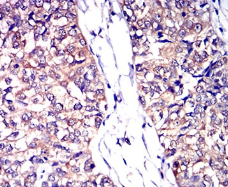

CD53 Mouse Monoclonal antibody[7A8D3]

IHC    1/200 - 1/1000